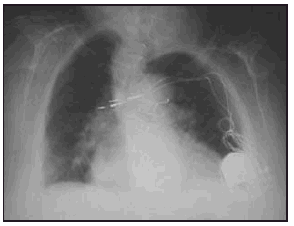

307 DOS CASOS DE SÍNDROME DE TWIDDLER

H.G. Fornieles Pérez, S. Martínez Escobar, F. Barredo Acedo, F.J. Guerrero Gómez y M. Montoya García

Servicio de CC y Urgencias del Hospital Torrecárdenas, Almería.

Introducción: una rara complicación de los pacientes portadores de marcapasos es el síndrome de Twiddler, que fue descrito en 1964 por Bayliss y cols como "spontaneous, subconcious, inadvertent, or deliberate rotation of de pulse generator by the patient resulting in lead dislogment and pacemacker malfunction". El generador es rotado en el eje vertical u horizontal y esto lleva a un enrollamiento de los electrodos que pierden el contacto con el endocardio.

Casos: presentamos dos casos clínicos de dos pacientes con este síndrome. Una paciente era una anciana con una demencia senil que un mes tras la implantación de un marcapasos acudió a nuestra consulta por estimulación en el hombro izquierdo y bajo gasto como consecuencia de la pérdida de captura del marcapasos. Se presentan las radiografías y fotografías intraoperatorias de los dos electrodos totalmente trenzados. El otro caso es el de una joven con un déficit intelectual moderado que presentó bajo gasto por la pérdida de captura del marcapasos implantado unos días antes. Se presentan radiografías del trenzado de los electrodos. En el primer caso la rotación del marcapasos fue en el eje vertical y en el segundo en el eje horizontal, en ambos casos se resolvió el caso reoperando a las pacientes y advirtiendo a las pacientes y a la familia sobre los riesgos de la manipulación del generador.